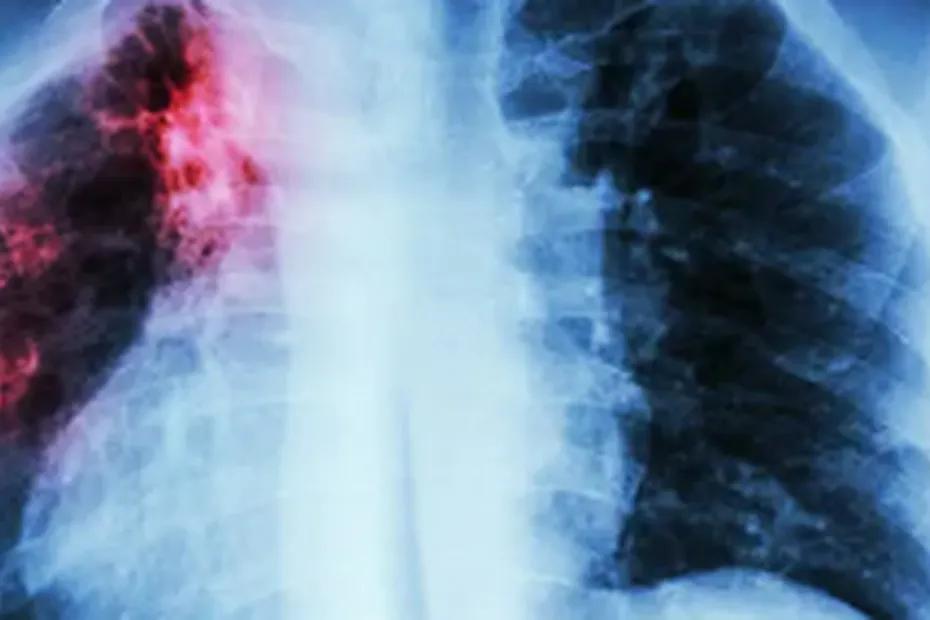

По словам биолога Юлии Кривошеевой, туберкулёз - это хроническое инфекционное заболевание, которое нередко протекает бессимптомно. Его возбудителем является микобактерия туберкулёза, или палочка Коха, способная длительное время сохраняться во внешней среде. Она может поражать практически все органы и системы организма, но чаще всего страдают лёгкие.